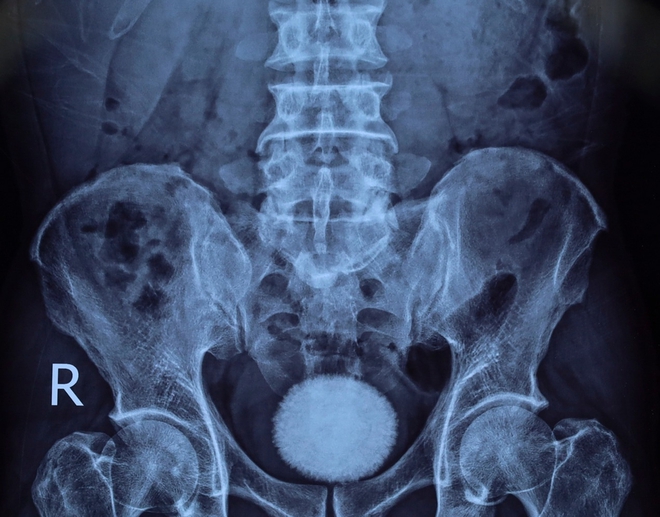

Trước đó, bệnh nhân đến khám trong tình trạng tiểu buốt, tiểu khó kéo dài, kèm đau vùng hạ vị. Qua thăm khám lâm sàng, siêu âm và chụp X-quang, các bác sĩ phát hiện trong bàng quang có viên sỏi kích thước khoảng 60x40 mm.

Viên sỏi bàng quang kích thước khoảng 60x40 mm được lấy ra sau phẫu thuật tại Bệnh viện Ngoại khoa 115 Nghệ An.